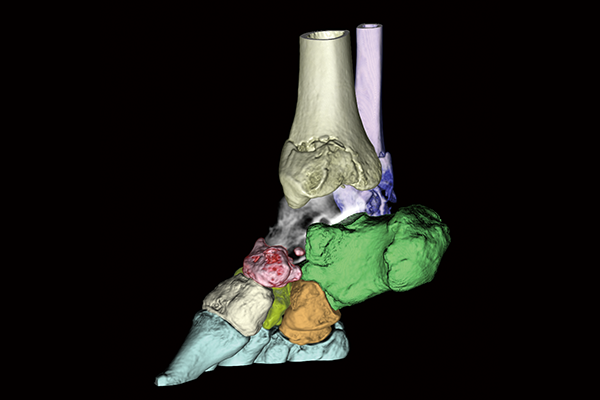

Bones are extracted or removed with one click based on the CT value and the shape of the region of interest recognized by REiLI technology.

Carpal bones removal

Lower extremity bones removal

Orthopedics